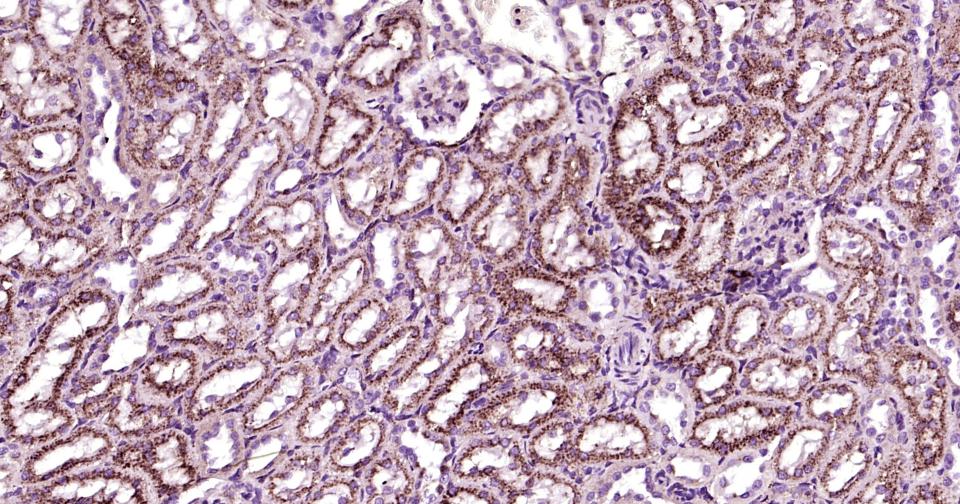

Paraformaldehyde-fixed, paraffin embedded Human kidney;Antigen retrieval by boiling in sodium citrate buffer (pH6.0) for 15 min; Antibody incubation with LAMP2 Monoclonal Antibody, Unconjugated (bsm-61207R) at 1:200 overnight at 4°C, followed by conjugation to the bs-0295G-HRP and DAB (C-0010) staining.